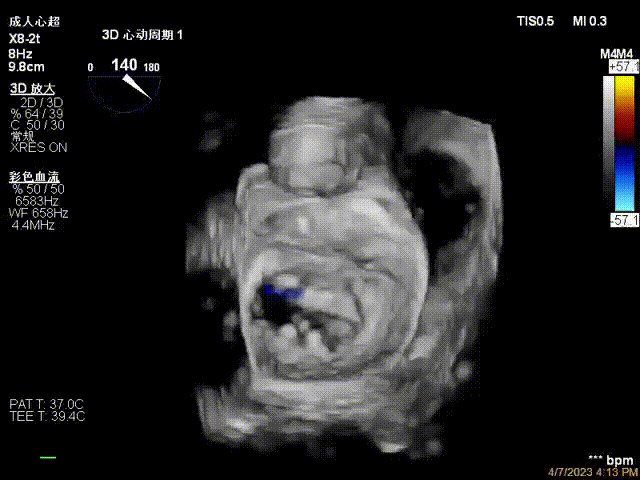

出院前隨訪超聲